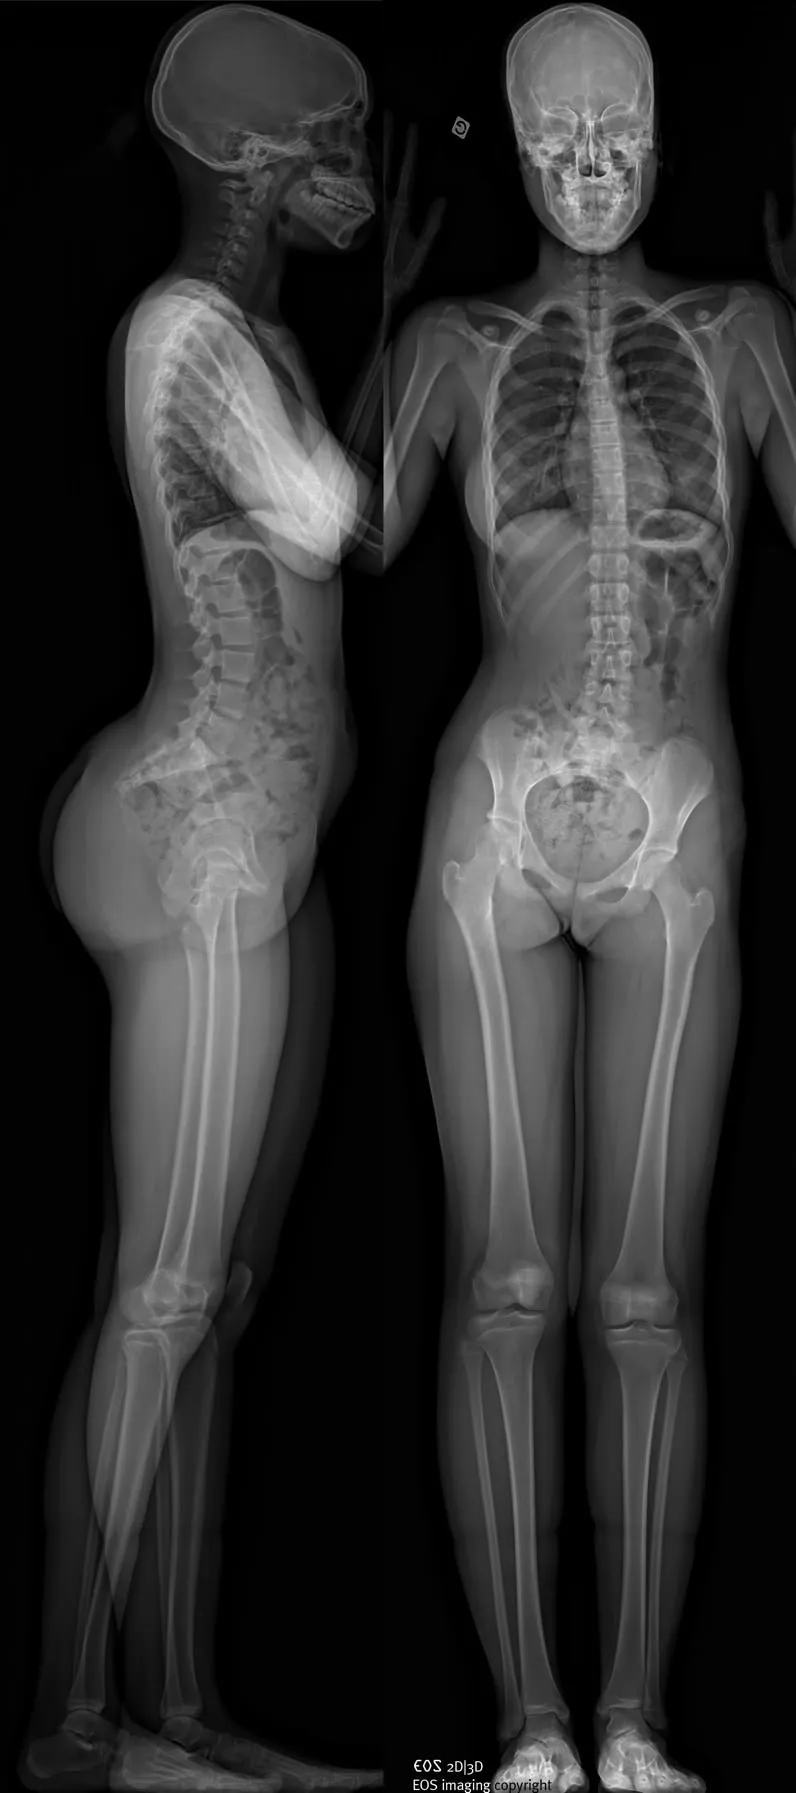

EOS réalise des radiographies du corps entier d’un patient en position debout, en une seule acquisition, sans assemblage d’images et sans distorsion verticale. Des clichés numériques de face et de profil, tout ou partie du corps, peuvent être obtenus simultanément, avec une qualité d’image exceptionnelle et sans aucun agrandissement pour une fiabilité parfaite des mesures.

Par un balayage de quelques secondes, une image de face et une de profil du corps entier en charge ou d’une zone anatomique choisie sont acquises simultanément. Un peu comme à la manière d’une photocopieuse, un très fin pinceau de rayons X balaye le corps du patient, de la tête aux pieds, simultanément de face et de profil.

Imagerie face/profil corps entier en charge

Non seulement l’examen est très peu irradiant, mais il est d’une exhaustivité que les examens conventionnels ne permettent pas d’atteindre. En effet l’acquisition se fait en charge (debout), de face et de profil, de façon parfaitement simultanée. Ces deux acquisitions peuvent être réalisées en charge mais aussi lors de manœuvres dynamiques. Cela permet une analyse statique et dynamique complète.